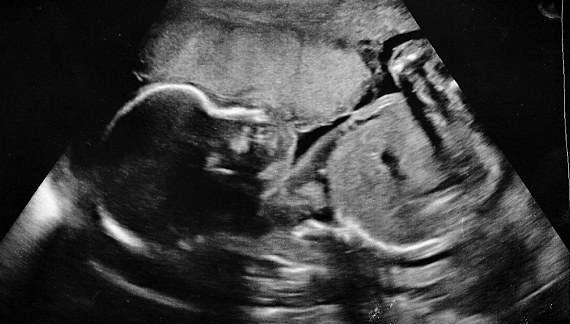

深爱孩子的父母可以为他做出任何事,一位英国的妈妈因为得知自己的羊水提早破裂,胎儿只剩5%机会可以存活,便每天开始喝多达3公升的水,让孩子能继续留在子宫,现在也健康地生下来了!

▼28岁的露依丝(Louise Adams)和丈夫生活在英国的史丹佛郡,他们本来都迫不及待迎接小儿子乔瑟夫(Joseph)的到来,但在22週的产检却得知,露依丝的羊水提早破裂了,胎儿恐怕无法存活。

▼在露依丝羊水破裂后,医生警告他们胎儿只剩5%的存活率,而且因为乔瑟夫还没来到比较稳定的24週,所以他们无计可施。露依丝和丈夫都对这样的结果相当震惊,但他们也同时决定,绝不放弃这个孩子。